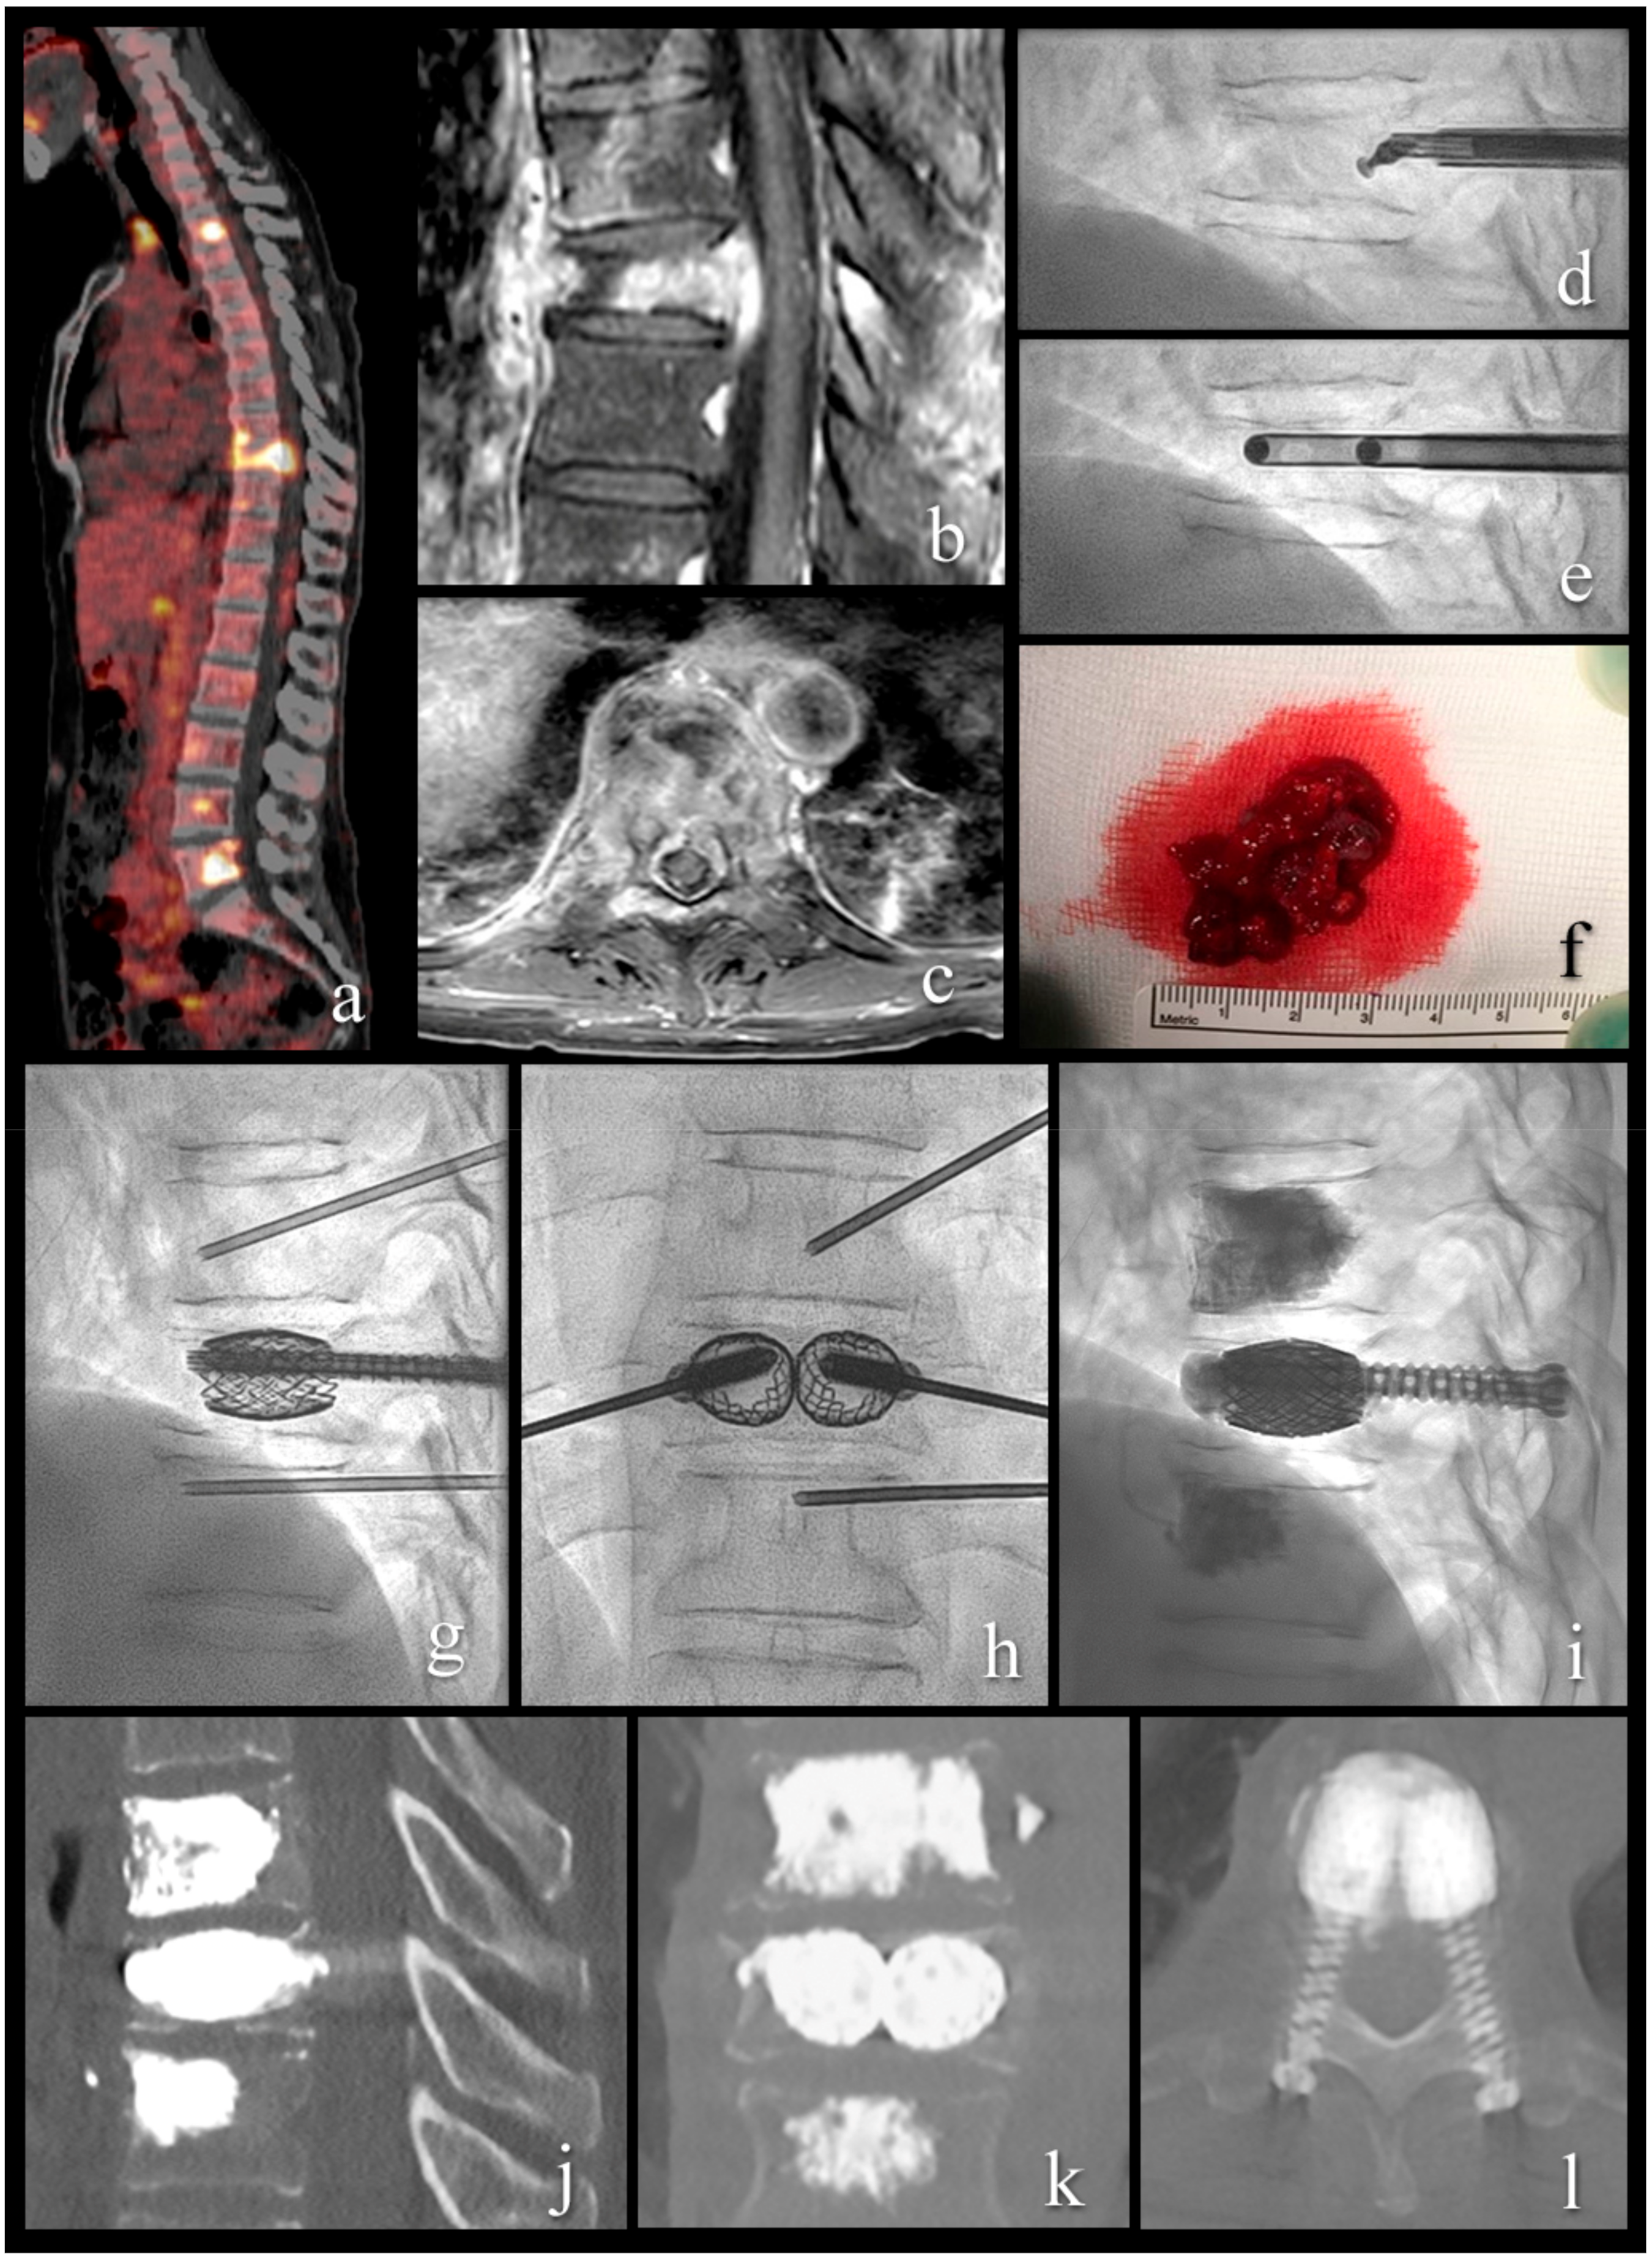

Figure 3.

A 54-year-old patient with metastatic renal cell cancer and acute onset back pain. (a) FDG PET-CT with multiple spinal lesions with increased FDG uptake. (b,c) sagittal and axial T1-weighted fat-suppressed enhanced MR images show the vertebral lesion with involvement of the posterior wall, an epidural mass, and pathologic fracture. (d) lateral fluoroscopy view with angulated curette in the vertebral body for lesion fragmentation. (e) lateral fluoroscopy view after introduction of two 10 G cannulas into the fragmented lesion for tumor flush and aspiration. (f) aspirated tumor soft tissue, histologically compatible with renal cell cancer metastasis. (g–i) lateral and anteroposterior fluoroscopy views with stent-screw assisted internal fixation (SAIF) and cement augmentation. (j–l) sagittal, coronal, and axial CT after SAIF.